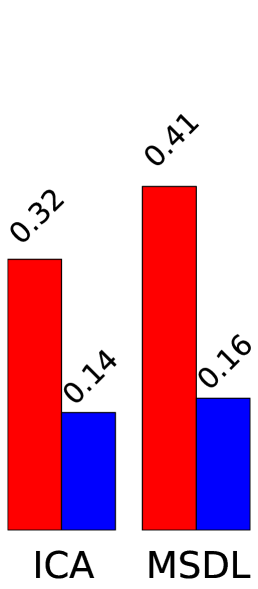

To quantify the usefulness of a set of regions extracted automatically, we consider metrics that characterize two different aspects of the segmentation: the ability to explain newly observed data and the reproducibility of the information extracted, as in the NPAIRS framework [7]. We use Explained Variance (EV) to measure how faithful the extracted regions are to unseen data. Stability with regards to inter-subject variability is measured using Normalized Mutual Information (NMI) over models learned on disjoint subsets of subjects.

Figure 2 presents region extraction results using each method on the same map. In all figures, the threshold applied during region extraction is shown in a given slice to help understanding. Results for each metric are displayed on the right. We vary parameters for each model (smoothing for ICA, 3 parameters of MSDL) and, for each region extraction method, display the best 10% results across parametrization. Figure 4 shows 2 networks out of 42 extracted.

Stability.

Random Walker dominates the stability metric. It uses local maxima to get regions seeds, and will thus split regions even if they are connected after thresholding. Its performance is statistically significant for both dense and sparse atlases and any parametrization. The stability improvement is larger for sparse than for dense maps. This could be due to the inability of random walker to compensate for the original instabilities of the models.

Data fidelity.

Starting from hard thresholding [2], we introduce richer strategies integrating spatial models, to avoid small spurious regions and isolate each salient feature in a dedicated region. Indeed, the notion of regions is hard to express with convex penalties. Relaxations such as total-variation used in [1] only captures it partially, while a non-convex segmentation step easily enforces regions. We find that a Random-Walker based strategy brings substantial increase in stability of the regions extracted, while keeping very good explanatory power on unseen data. Finer results and interpretation may arise by using more adapted metrics, for example a version of DICE that can deal with overlapping fuzzy regions. This point is under investigation.